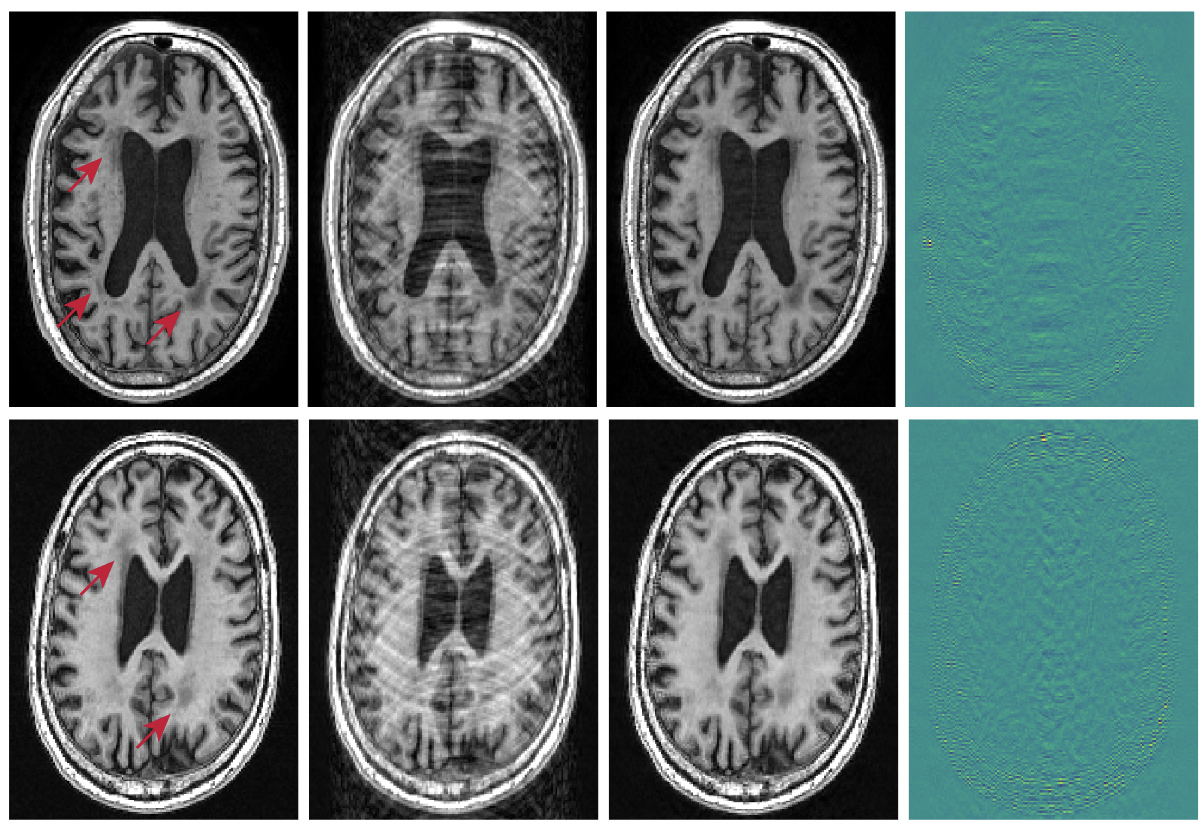

Unsupervised Anomaly Detection in Medical Imaging using Aggregated Normative Diffusion

Alexander Frotscher, Jaivardhan Kapoor, Thomas Wolfers, Christian F. Baumgartner

Medical Image Analysis, 103895 (2025)

Deep Unsupervised Anomaly Detection in Brain Imaging: Large-Scale Benchmarking and Bias Analysis

Alexander Frotscher, Christian F. Baumgartner, Thomas Wolfers

arXiv preprint arXiv:2512.01534 (2025)